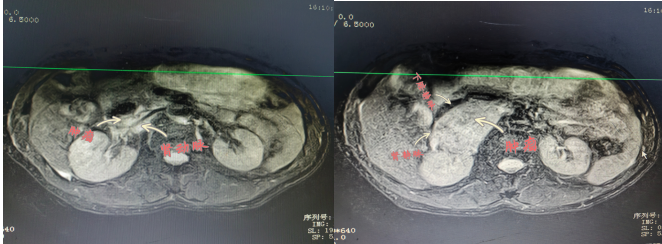

患者陽(yáng)某,67歲,8月2日因“反復(fù)胸悶氣促2年余,再發(fā)伴頭暈黑蒙3天?!本驮\于衡陽(yáng)市中心醫(yī)院心血管內(nèi)科,患者血壓波動(dòng)大,最高值199/118mmHg,最小值98/57mmHg,射血分?jǐn)?shù)最低42%;完善相關(guān)檢查發(fā)現(xiàn)右腎上腺巨大腫物,大小約57×73×75mm,遂轉(zhuǎn)入衡陽(yáng)市中心醫(yī)院泌尿外科治療,泌尿外科醫(yī)護(hù)團(tuán)隊(duì)前期做了充分的準(zhǔn)備,并進(jìn)行科內(nèi)討論,麻醉科、心血管內(nèi)科專(zhuān)家會(huì)診,充分予以穩(wěn)定血壓、心率和擴(kuò)容等術(shù)前處理。

2022年9月15日,醫(yī)院為患者行腹腔鏡下右側(cè)腎上腺瘤腫瘤切除術(shù),術(shù)中,患者右側(cè)腎上腺腫瘤于腎門(mén),壓迫下腔靜脈,右腎靜脈移位,包繞右腎動(dòng)脈。腫瘤體積大,血運(yùn)豐富與周?chē)M織邊界不清, 與大血管粘連,手術(shù)風(fēng)險(xiǎn)極大,術(shù)中鉗夾,擠壓腎上腺瘤體導(dǎo)致腎上腺激素釋放,手術(shù)中血壓的急劇變化。充分顯露手術(shù)視野,仔細(xì)、輕柔操作對(duì)腫瘤切除十分關(guān)鍵。麻醉科主任譚滇湘全程護(hù)航。由于準(zhǔn)備充分、配合到位,雖術(shù)中情況多變,最終手術(shù)成功。術(shù)后病檢結(jié)果顯示腫瘤完整切除?;颊咝g(shù)后恢復(fù)良好,于2022年9月24康復(fù)出院。